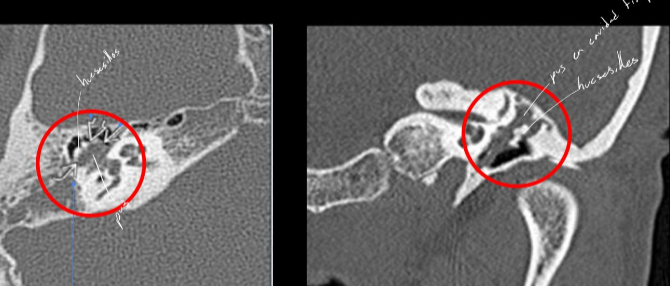

Colesteatoma

Neoplasia de tejido epidermico q crece en el interior del conducto auditivo

- se forma despues de una infección

- Benigno pero con comportamiento maligno → destruye hueso y cadena osicular

- Clx: dolor retroauricular, sordera, meningitis

estudio de imagen de colesteatoma

TC y RM

- Masa que destruye hueso